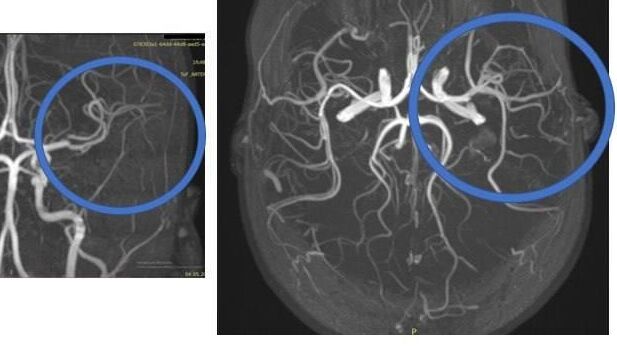

УФА, 14 окт - РИА Новости. Московские врачи из федеральных центров провели шесть телемедицинских консультаций с уфимскими коллегами по девочке, которую отец сбросил с высоты, ребёнок остается в реанимации в крайне тяжёлом состоянии, сообщил министр здравоохранения Башкирии Айрат Рахматуллин.

"Трехлетняя девочка, которая пострадала при падении с высоты, по-прежнему находится в реанимации в крайне тяжелом состоянии", - написал Рахматуллин в своём Telegram-канале.

Он добавил, что врачам удалось стабилизировать ее состояние.

"Проведено уже шесть телемедицинских консультаций с федеральными центрами – с Российской детской клинической больницей имени Пирогова и Национальным медицинским исследовательским центром имени

Леонида Рошаля. В ближайшее время будут проведены обследования, чтобы отследить состояние в динамике", - отметил региональный министр.

Утром 9 октября на улице Ульяновых в

Уфе 34-летний мужчина сбросил с четвертого этажа своего ребенка, ранее он наблюдался у психиатра. Трехлетняя девочка в крайне тяжелом состоянии была госпитализирована, ее прооперировали. Подозреваемого задержали. Возбуждено уголовное дело о покушении на убийство.